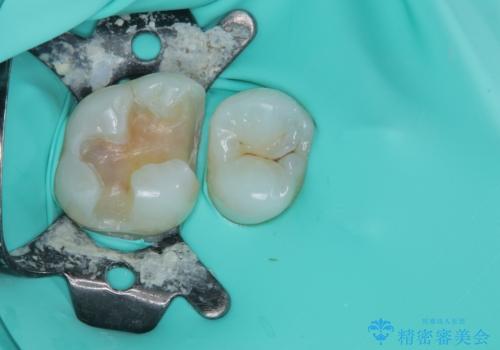

虫歯になってしまっているところをしっかりと除去し、形を整えて、精度の高いシリコーンによる型どりを行いました。

また、インレー接着時には唾液や血液による接着力の低下を防ぐためにラバーダム防湿を行っています。